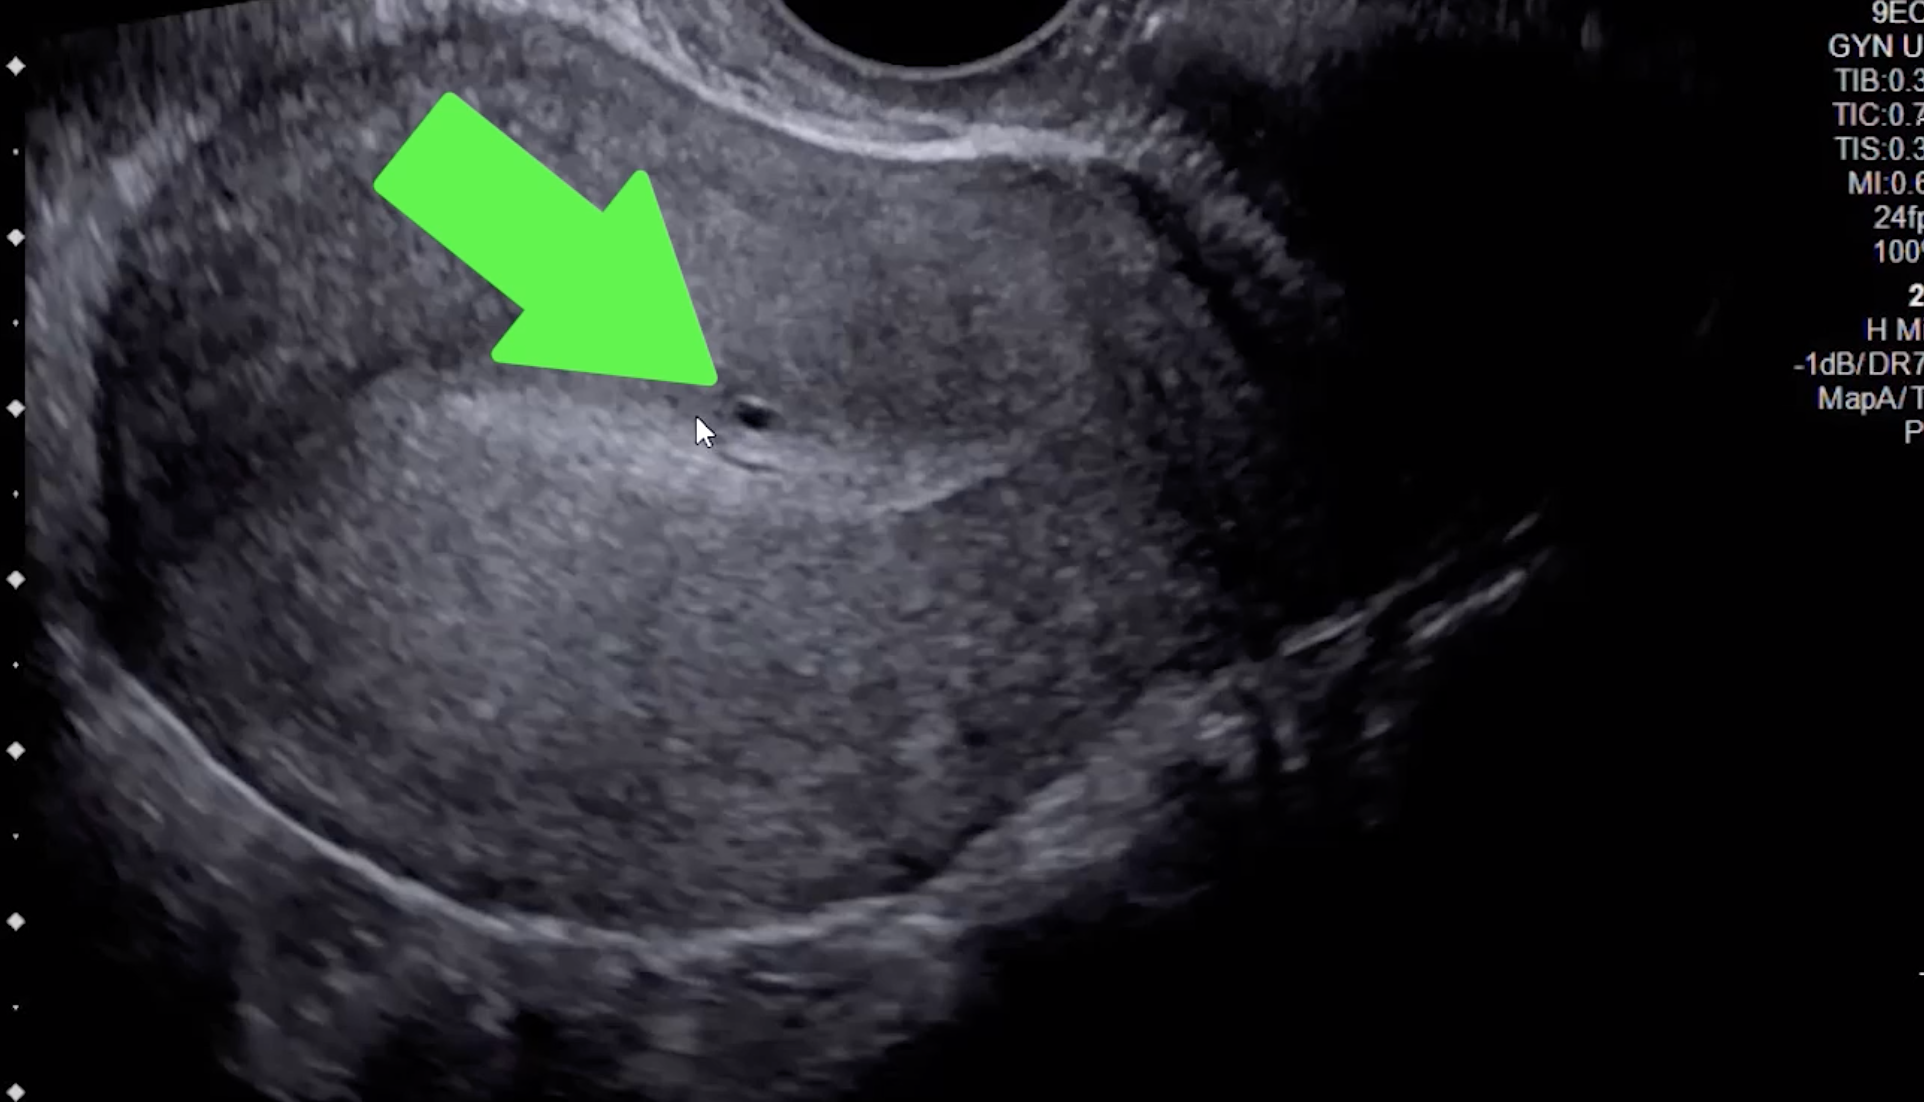

• Echogenic nodules/striations or small cysts (US to R)

• Small cysts at the endometrial-myometrial junction are most sensitive & specific finding for adenomyosis (green arrow)